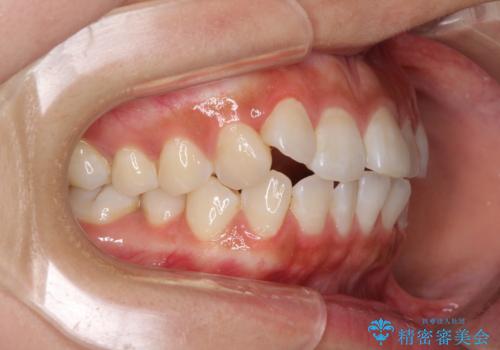

- 上下前歯のデコボコを気にして来院された患者様です。

インビザラインによる上下歯列の拡大と、IPR(歯と歯の間を削る)にるスペースの獲得により、前歯のデコボコを改善することとしました。